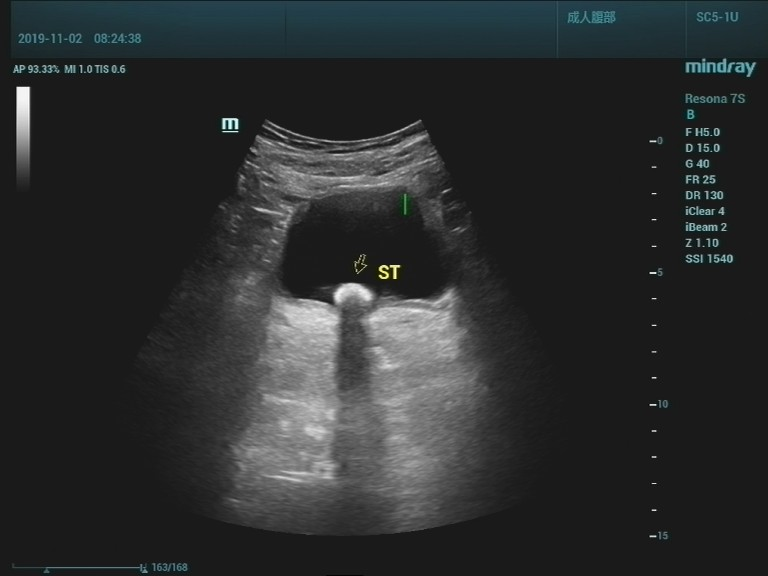

泌尿系结石

夏季到了,急诊室内面色苍白,捂着肚子,额头沁满汗珠的患者越来越多了,见到医生的第一句就是“医生,我的结石又痛了!” 泌尿系结石是一种常见病,多发病,医学上把肾脏结石、输尿管结石、膀胱结石和尿道结石统称为尿路结石。男性发病率明显高于女性。 01 尿路结石常见的病因 1.个体因素和遗传因素。 2.长期在高温环境中工作,机体水份蒸发多,尿液浓缩,容易形成结石。 3.代谢性疾病,如甲状旁腺功能亢进,尿中钙盐增多;痛风病人尿中尿酸盐增加,均易得结石。 4.某些食物或药物的长期作用使尿液酸碱度改变,也是结石生成的一种诱因。 5.前列腺增生或其他原因引起的排尿不畅,慢性尿潴留,因尿液浓缩尿液中盐份容易沉积,形成结石。 6.长期卧床,因骨质脱钙,血钙浓度增加易致结石形成。 结石的诱发因素多种多样,因此结石的预防也要有针对性。结石成分的分析有助于明确病因。盲目忌口对预防结石收效不明显。这里顺带一句,很多病人误认为柿子吃多了会得尿路结石,实际上这是一种讹传,柿子吃多了可能会凝结成胃肠道柿石,而与泌尿系结石完全没有关系。 02 泌尿系结石发作时的症状和体征 泌尿系结石原发部位一般都在肾脏内,平时不会有什么感觉,只有等结石掉入到肾盂出口处或输尿管内,引起输尿管梗阻和痉挛时才会出现一系列症状和体征。输尿管结石常停留于上端、下端及髂血管旁三个生理性狭窄处,结石对管壁的摩擦和刺激,可导致输尿管局部粘膜损伤、水肿甚至并发炎症。 结石疼痛常常呈突发性,表现为一侧腰部或腹部刀绞样疼痛,多数疼痛剧烈难忍,部分病人疼痛可放射至腹股沟区或会阴部。可伴有恶心呕吐、血尿,尿频、尿急、尿痛及反射性少尿。 体征表现为面色苍白,痛苦病容以及腰痛特有的姿势,检查可有肾区叩击痛。少数输尿管结石病人可以长期没有明显症状,往往要等到健康检查时才发现。 泌尿系结石的诊断:泌尿系统结石诊断并不难,一般通过超声或CT检查就能明确结石的大小和部位,肾输尿管有无扩张、积水。尿检有无红细胞可作为参考依据。 肾结石 肾积水 输尿管结石 膀胱结石 03 泌尿系统结石的治疗 1. 肾脏结石比较大的,或数量较多的,或伴有积水的可考虑外科微创或手术治疗。肾结石较小的一般没有症状也不影响肾脏功能,可不作处理。 2.输尿管结石不管在哪个部位,基本上都有不同程度的输尿管扩张和肾脏积水,时间久了积水可能会加重,影响肾脏功能。因此输尿管结石一经确诊一定要尽早治疗。0.5--0.6cm及以下的结石如果疼痛不是很厉害可以选择药物排石,但切记要间隔一星期左右复查,直到结石排出。较大的结石或保守治疗不能排出的结石可首先考虑体外冲击波碎石治疗。 3.膀胱结石最大径在3cm以下且前列腺增生不明显的可考虑体外碎石治疗。结石过大,或前列腺增生显著的可选择钬激光治疗或膀胱切开取石。 泌尿系结石虽然不算什么大病,但发作时疼痛是最剧烈的,大多需要急诊处理。体外冲击波碎石具有简便快捷,疗效确切,安全性高、痛苦较小、费用合理等优势,病人普遍容易接受,可以作为治疗泌尿系结石的首选。少数病人碎石后结石仍无法排出,或者是结石被包裹的病人则需要泌尿外科进一步处理。 输尿管结石碎石后呈长条状 敲黑板啦——预防结石有妙招●● 1.养成多饮水的习惯。多饮水可稀释尿液,降低尿内各种盐类的浓度。水源的改善对结石的预防也有一定的意义。 2.尽早除去尿路梗阻因素,如前列腺增生症、尿道狭窄等。 3.积极、规范、彻底治疗泌尿系的感染性疾病。 4.长期卧床的病人,应鼓励多活动,勤翻身,减少骨质脱钙。 5.有甲状旁腺机能亢进者,应积极治疗。